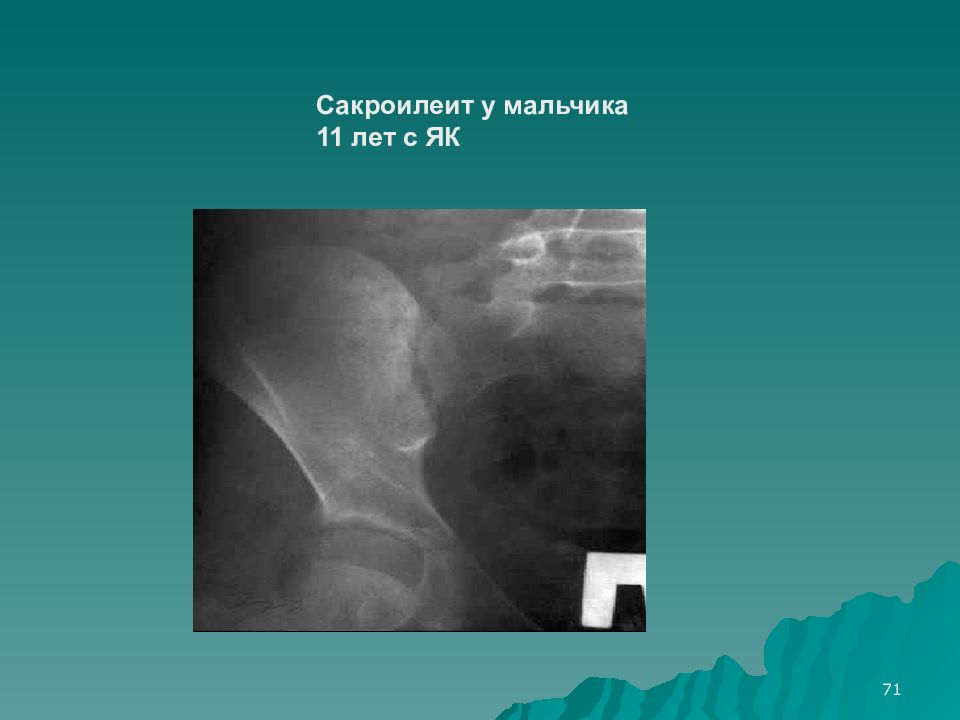

Фотографии и изображения, связанные с симптомами первичного склерозирующего холангита